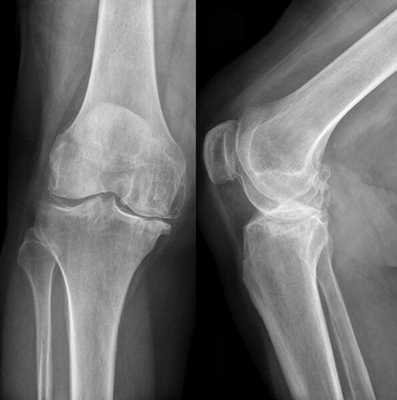

Рентгенографическая визуализация

- Рентгенографии. Ранее самым доступным и зачастую единственным способом инструментальной диагностики при разрывах менисков была рентгенография коленного сустава с использованием контрастного вещества. Такое исследование позволяло уточнить локализацию, вид и размер повреждения.